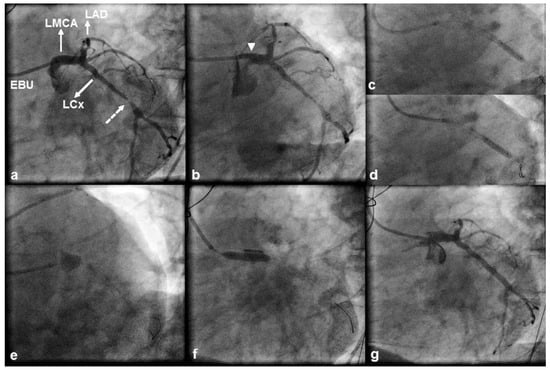

A 71 year old, male patient was referred for coronary angiography because of non ST segment elevation myocardial infarction. The echocardiogram performed at the referring hospital showed hypokinesia of the inferior, inferior septal and lateral left ventricular walls with an ejection fraction of 40%. The patient had a history of hypertension, hyperlipidaemia, inferior myocardial infarction and bare metal stent facilitated PCI of a dominant right coronary artery (RCA) and the proximal and distal left circumflex (LCx) artery. In 2011, he underwent CABG with a left internal mammary artery graft to the left anterior descending (LAD) artery and a saphenous vein graft to a diagonal artery; preoperatively, no significant viability was documented with low dose dobutamine echocardiography over the dependent myocardium of the chronically occluded, yet collateralised RCA demonstrated during angiography. Transfemoral angiography during the current admission revealed patent grafts and obstructive in stent disease of the proximal LCx artery culminating in a tight lesion just distal to the outflow of the stent (Figure 1a). Therefore, we proceeded with PCI to the LCx artery. The LMCA was engaged without difficulty with a 6 French Extra Back up (EBU) 4.0 guiding catheter and, after predilation, a 3.5 × 33 mm DES was uneventfully deployed across the lesion (Figure 1b). Because of stent underexpansion at the site of the tight lesion we successfully performed postdilation with use of a 3.75 × 15 mm noncompliant balloon (Figure 1c). A second postdilation was then performed at a more proximal location (Figure 1d), yet subsequent angiography revealed persistent contrast staining outside the coronary lumen at the site of the LMCA ostium, which was compatible with a type C coronary dissection (Figure 1e). The patient was pain free and haemodynamically stable without electrocardiographic evidence of ischaemia. The dissection was immediately tackled with a 4.5 × 18 mm DES (Figure 1f). Postdilation was carried out with a 5.0 × 15 mm noncompliant balloon and final angiography showed complete sealing of the dissection flap (Figure 1g). Postprocedural creatine kinase and creatine kinase MB isoenzyme levels were normal. The patient had an uneventful 2 day hospital course and was discharged home on life long dual antiplatelet therapy. He remained stable 3.5 years post stenting with Canadian angina class I and no evidence of a cardiovascular event.

Figure 1. (a) 45° left anterior oblique (LAO) view of the left coronary artery displaying a tight left circumflex (LCx) artery lesion (dashed arrow) located just distal to a previously implanted bare metal stent. A 6 French Extra Back-up (EBU) 4 guiding catheter is seen engaged in the ostium of a minimally diseased left main coronary artery (LMCA). The left anterior descending (LAD) artery, which contains a mid segment occlusion, is also shown. (b) LAO angiogram showing the stent deployment position. Note the unfavourable position of the guiding catheter resulting in the tip abutting against the wall of the LMCA ostium (arrow). Compared with its position during the first postdilation (c), the tip of the guiding catheter was too deep-seated during the sec- ond postdilation (d). (e) 40° LAO and 40° caudal view depicting persistent extraluminal contrast staining at the site of the LMCA ostium (type C coronary dissection). (f) Stent deployment across the dissection. (g) 45° LAO view showing an optimal angio- graphic result with complete sealing of the dissection flap.

The RCA is the most frequently dissected vessel (84– 87% of the cases), followed by the LAD, left main coronary and LCx arteries [16,17]. Iatrogenic dissection of both the RCA and LMCA is mostly observed after inadequate alignment of a diagnostic or guiding catheter (1,2,4), yet the LMCA and RCA arise from their respective aortic sinuses at different angles: acute (range 20°– 55°) and almost perpendicular (range 60°–88°), respectively. This might render the LMCA less susceptible to catheter induced dissection by providing a better approach for catheterisation [17]. Three retrospective case series have reported the incidence of iatrogenic LMCA dissection during a coronary catheterisation procedure (PCI or diagnostic coronary angiography). Lee et al. [1] reported an incidence of 0.03% (10 cases out of 34 190 procedures), Cheng et al. [2] an incidence of 0.071% (13 cases out of 18 400 procedures), and Eshtehardi et al. [4] an incidence of 0.07% (38 cases out of 51 452 procedures) with a twofold greater incidence of iatrogenic LMCA dissection during PCI (0.1% of all PCIs) than during diagnostic coronary angiography (0.06% of all diagnostic coronary angiographies). Dissection of the LMCA is most frequently caused by inappropriate positioning of the diagnostic or guiding catheter, with an incidence of 61.5% in the study by Cheng et al. [2] where a 6 French catheter was used in 84.6% of the cases, the Kimny miniradial catheter in 61.5% of the cases and the left Judkins catheter in 30.8% of the cases. Balloon dilation near the LMCA bifurcation and stenting at the LAD artery ostium were the second and third most frequent causes of LMCA dissection in this study, with an incidences of 23.1% and 7.7%, respectively. In the study by Eshtehardi et al. [4], inappropriate positioning of a diagnostic catheter was implicated in 58% of the cases of LMCA dissection where the left Judkins catheter was used in 82% of the cases; inappropriate positioning of a guiding catheter was implicated in 16% of the cases of LMCA dissection where extra backup catheters (Amplatz left , EBU- or Q curve) were used in 56% of the cases. The second most frequent cause of LMCA dissection in this study was deep intubation of the guiding catheter during balloon retrieval, which was observed in 26% of the cases. In our first case, as shown in Figure 1b, the 6 French EBU 4.0 guiding catheter was non coaxially positioned and its tip abutted against the wall of the LMCA ostium without, however, causing pressure damping or ventricularisation. However, such a catheter position suggested that the catheter might have been “too short” for the patient and that a more coaxial LMCA engagement could have been achieved with an EBU 4.5 guiding catheter. Dissection of the LMCA occurred secondary to deep seeding of the guiding catheter and scraping of the LMCA wall during retrieval of the postdilating balloon. If we had disengaged the guiding catheter from the LMCA and pulling, to keep the catheter out of the LMCA ostium, had been more vigorous to withstand the resistance met during retrieval of the postdilating balloon, we would have prevented deep seeding of the guiding catheter and the resultant LMCA dissection. In our second case, the LMCA contained substantial, but nonobstructive atheroma. As shown in Figure 1d, the 6 French EBU 4.0 guiding catheter was non coaxially positioned with its tip pointing vertically against the roof of the LMCA. Accordingly, a hydraulic LMCA dissection might have been created during contrast injection. Keeping the catheter coaxially positioned during every minute of the procedure, avoiding contrast media injection in the presence of pressure damping or ventricularisation and gradual ramping of the injection are essential actions in order to minimise the risk of LMCA dissection.